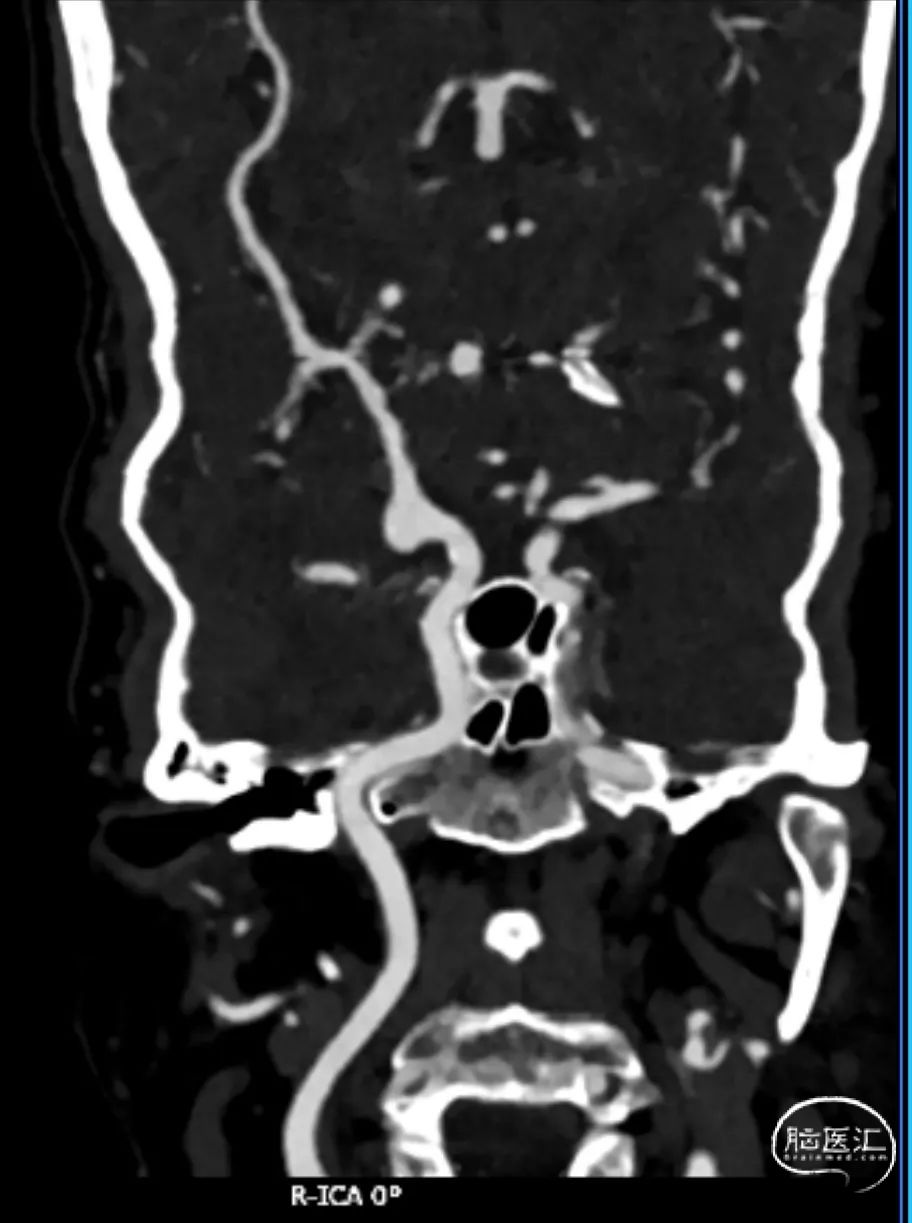

简要病史:患者近2周前体检行核磁MRI检查发现右侧颈内动脉动脉瘤,进一步完善头颅CTA检查明确为右侧颈内动脉C7段动脉瘤。

CTA:右侧颈内动脉C7段动脉瘤。

老年女性患者,检查发现右侧颈内动脉C7段大动脉瘤,动脉瘤直径大于10mm,形态不规则,宽颈,手术指征明确,既往高血压、肿瘤病史,首选微创介入手术,术中造影证实动脉瘤直径大于10mm,绝对宽颈,形态不规则,局部仔瘤改变,右侧脉络膜前动脉从瘤体发出;微创介入血流导向装置是较优选择。